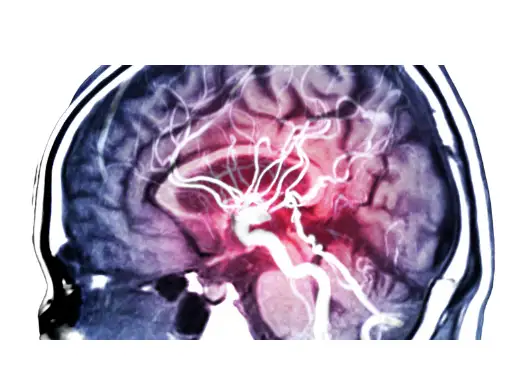

오늘은 뇌경색 초기증상, 원인 및 치료 방법에 대해 포스팅을 해보겠습니다. 뇌경색은 뇌에 혈액을 공급하는 혈관이 터지거나 막힘으로 인해 산소공급이 차단되어 뇌조직이 손상되는 증상을 말합니다.

뇌졸중이라고도 하며, 우리나라에서는 흔히 '중풍'이라는 말로도 불립니다. 뇌경색의 초기증상은 매우 다양하며 갑작스럽게 발생하는 경우가 대부분입니다. 그럼 뇌경색 초기증상 알아보겠습니다.